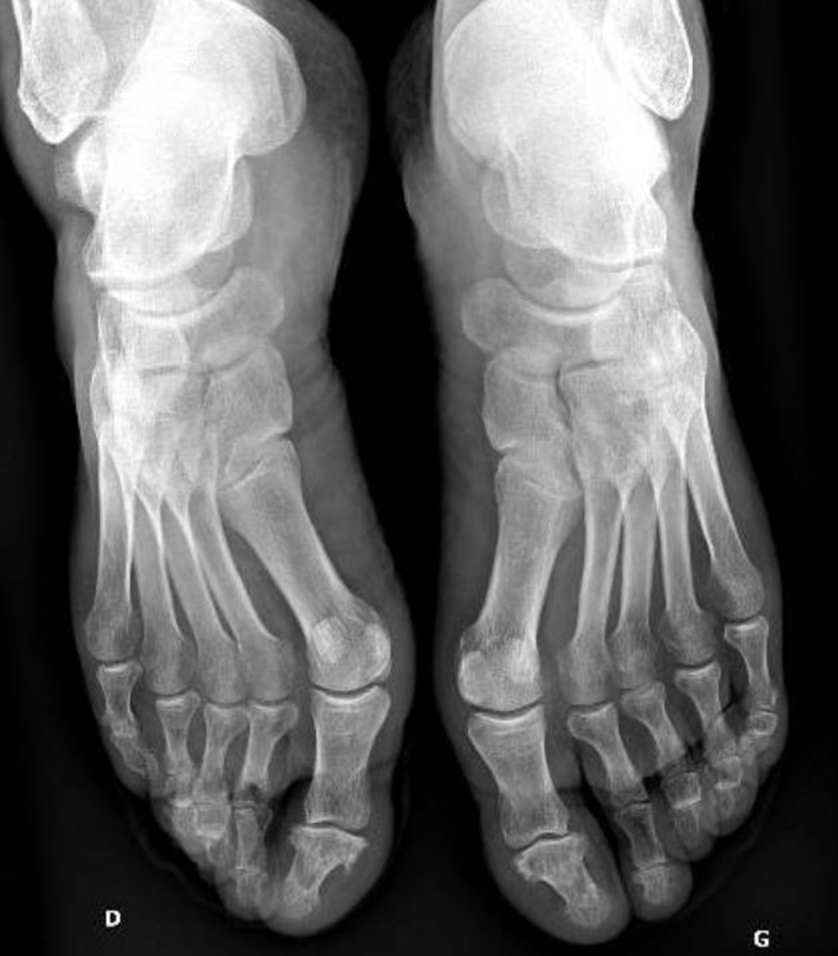

Le patient revient une semaine plus tard avec les examens prescrits. Biologie : hémoglobine = 13,4 g/dL ; leucocytes = 9 G/L avec formule leucocytaire normale ; plaquettes = 238 G/L ; aspartate aminotransférase (ASAT) 24 UI/l ; alanine aminotransférase (ALAT) = 25 UI/l ; gamma-glutamyl transférase (GGT) = 84 UI/L ; phosphatases alcalines (PAL) = 226 UI/L ; bilirubine totale = 8 µmol/L ; créatinine = 81 µmol/L, soit un débit de filtration glomérulaire (DFG) à 96 mL/min ; protéine C réactive (CRP) = 14 mg/L ; uricémie = 401 µmol/L ; facteurs antinucléaires (FAN) = 1/80 ; facteurs rhumatoïdes (FR) et anti-peptides cycliques citrullinés (anti-CCP) négatifs. Ponction du genou : 8 600 éléments, pas de cristaux, culture négative à 48 heures. Les radiographies des genoux sont normales, notamment pas de pincement, pas d’érosion, pas de méniscocalcose. Les radiographies des pieds sont les suivantes : Figure 3 (Source : Salomé Abdellaoui, La Revue du Praticien) L’échographie des pieds confirme la dactylite du 3e orteil droit et ne retrouve pas d’autre anomalie.

L’association d’une oligo-arthrite chronique, d’une dactylite, et d’un psoriasis oriente vers le diagnostic de rhumatisme psoriasique. Les radiographies des pieds sont normales à l’exception d’un ostéophyte de la dernière phalange du premier rayon droit, évocateur d’arthrose. Dans le rhumatisme psoriasique évolutif, il est classique de retrouver des lésions destructrices et reconstructrices. Les autres diagnostics sont beaucoup moins probables devant l’absence de marqueurs d’auto-immunité, de cristaux à la ponction, d’érosions caractéristiques radiographiques.

Les radiographies ici sont normales et n’orientent donc pas le diagnostic.